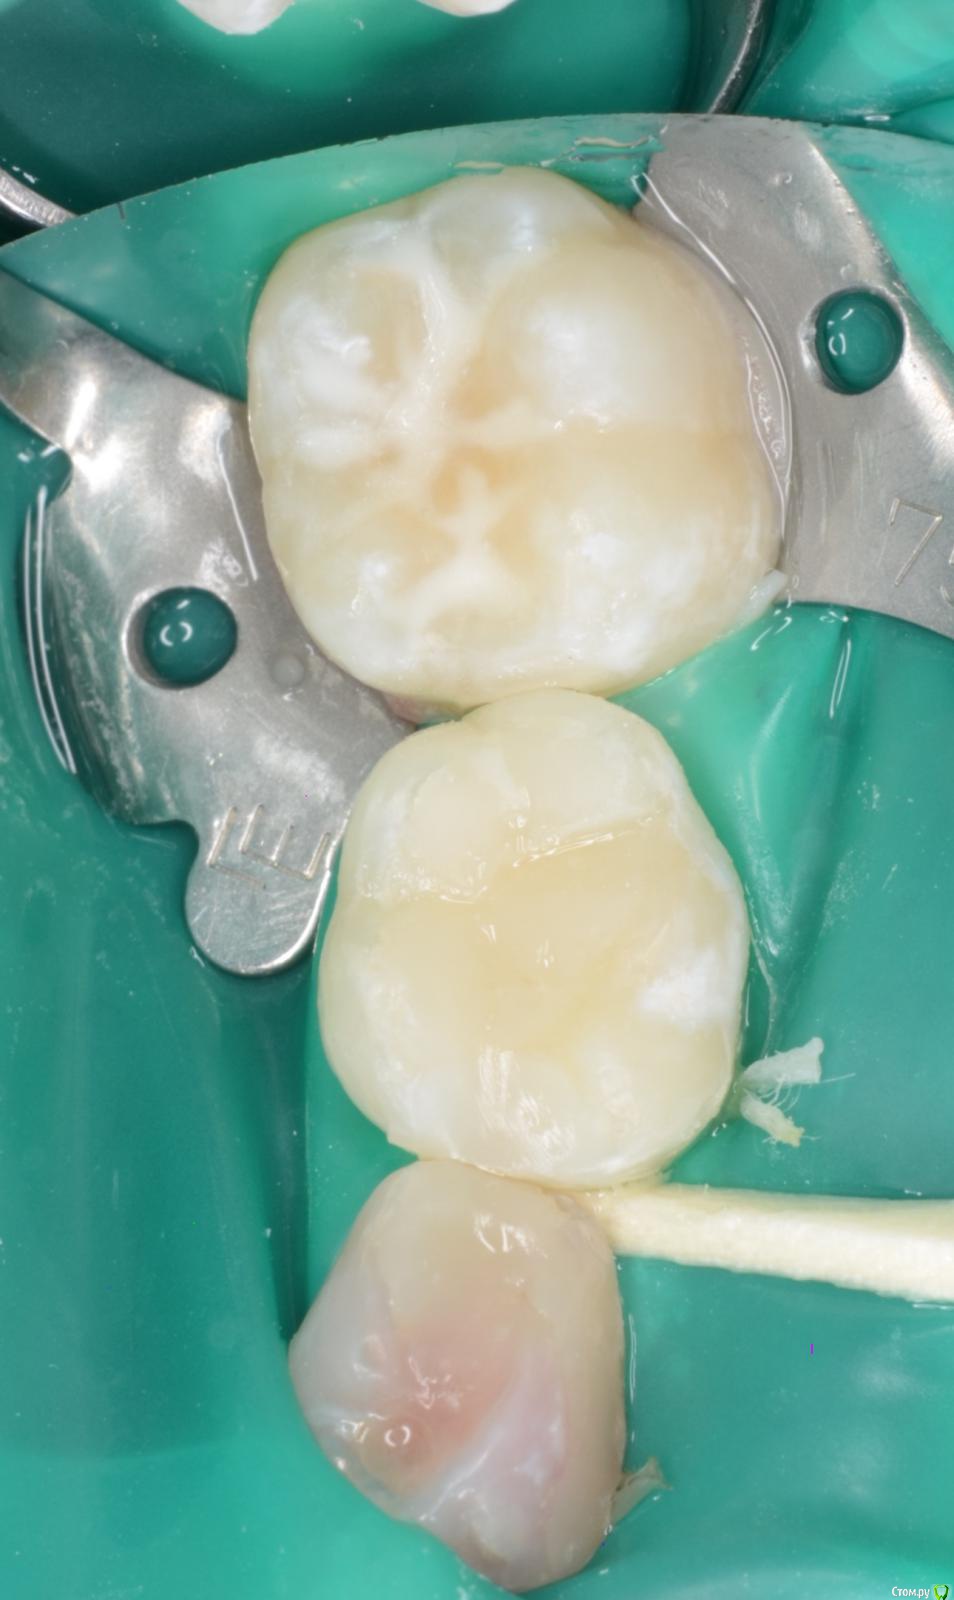

CRAZYDUCK Опубликовано 19 мая, 2018 Автор Поделиться Опубликовано 19 мая, 2018 Лечение кариеса 8.4 и 8.5 , герметизация 4.6 . 3 Ссылка на комментарий

CRAZYDUCK Опубликовано 19 мая, 2018 Автор Поделиться Опубликовано 19 мая, 2018 (изменено) Костя , 7 лет .Лечение кариеса 1.6; обратимый пульпит 5.4 и 5.5 .5.4 заполирован по контакту после снятия коффера, платок два раза меняла ( порвала по каоьакту). Фото после снятия коффердама уже не было сил сделать ;( ( новая ассистент, еще не сработались - дольше все делаем , чем с другим ассистентом .Ещё прийдет на лечение - сделаю . Изменено 19 мая, 2018 пользователем CRAZYDUCK 3 Ссылка на комментарий